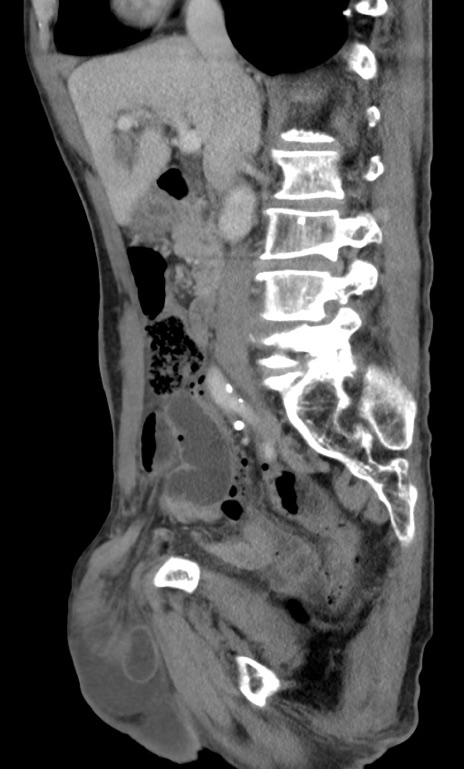

横断像

【症例】 70歳代男性

【主訴】右鼠径部腫瘤、疼痛

【既往歴】膀胱癌にて膀胱全摘、両側尿管皮膚瘻